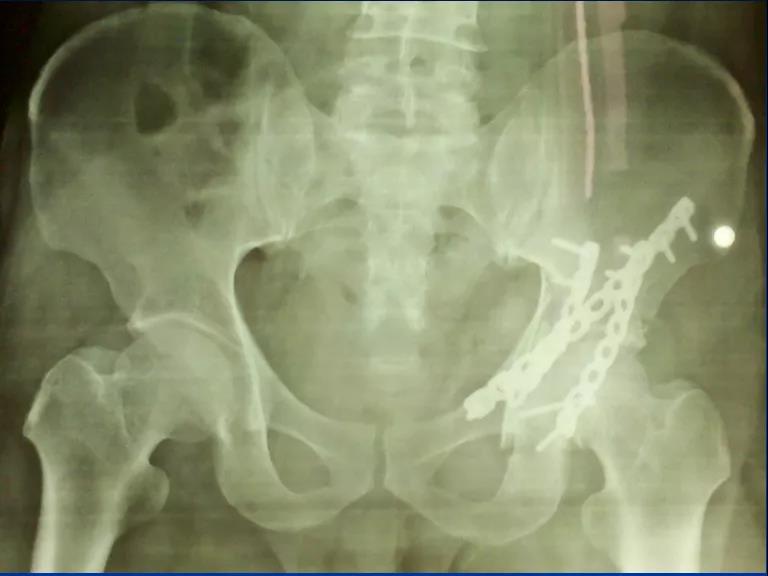

5、根据CT情况探查关节腔,清除关节内的碎骨片; 6、a:解剖复位髋臼后柱及后壁;b:以重建钢板固定 c:纱布填塞切口 d:行C型臂透视了解前壁或前柱骨折复位情况;

7、后柱后壁解剖复位后,由于关节囊完整,前柱一般都能自然复位,对于后柱复位后,前柱骨折移位仍明显且复位该部位能明显修复整个髋臼的解剖序列和减少术后并发症的枢纽部位作为前入路的切开部位。前入路微创切口沿髂耻嵴插板,行前柱重建钢板内固定;

10、沿髂耻嵴插板,在耻骨上支用2枚螺钉固定,维持前柱,前壁解剖序列连续性,再髂骨上固定另一枚螺钉,起到断端加压作用。

——典型案例——

微创插板病历后路有限切开,结合前路微创插板内